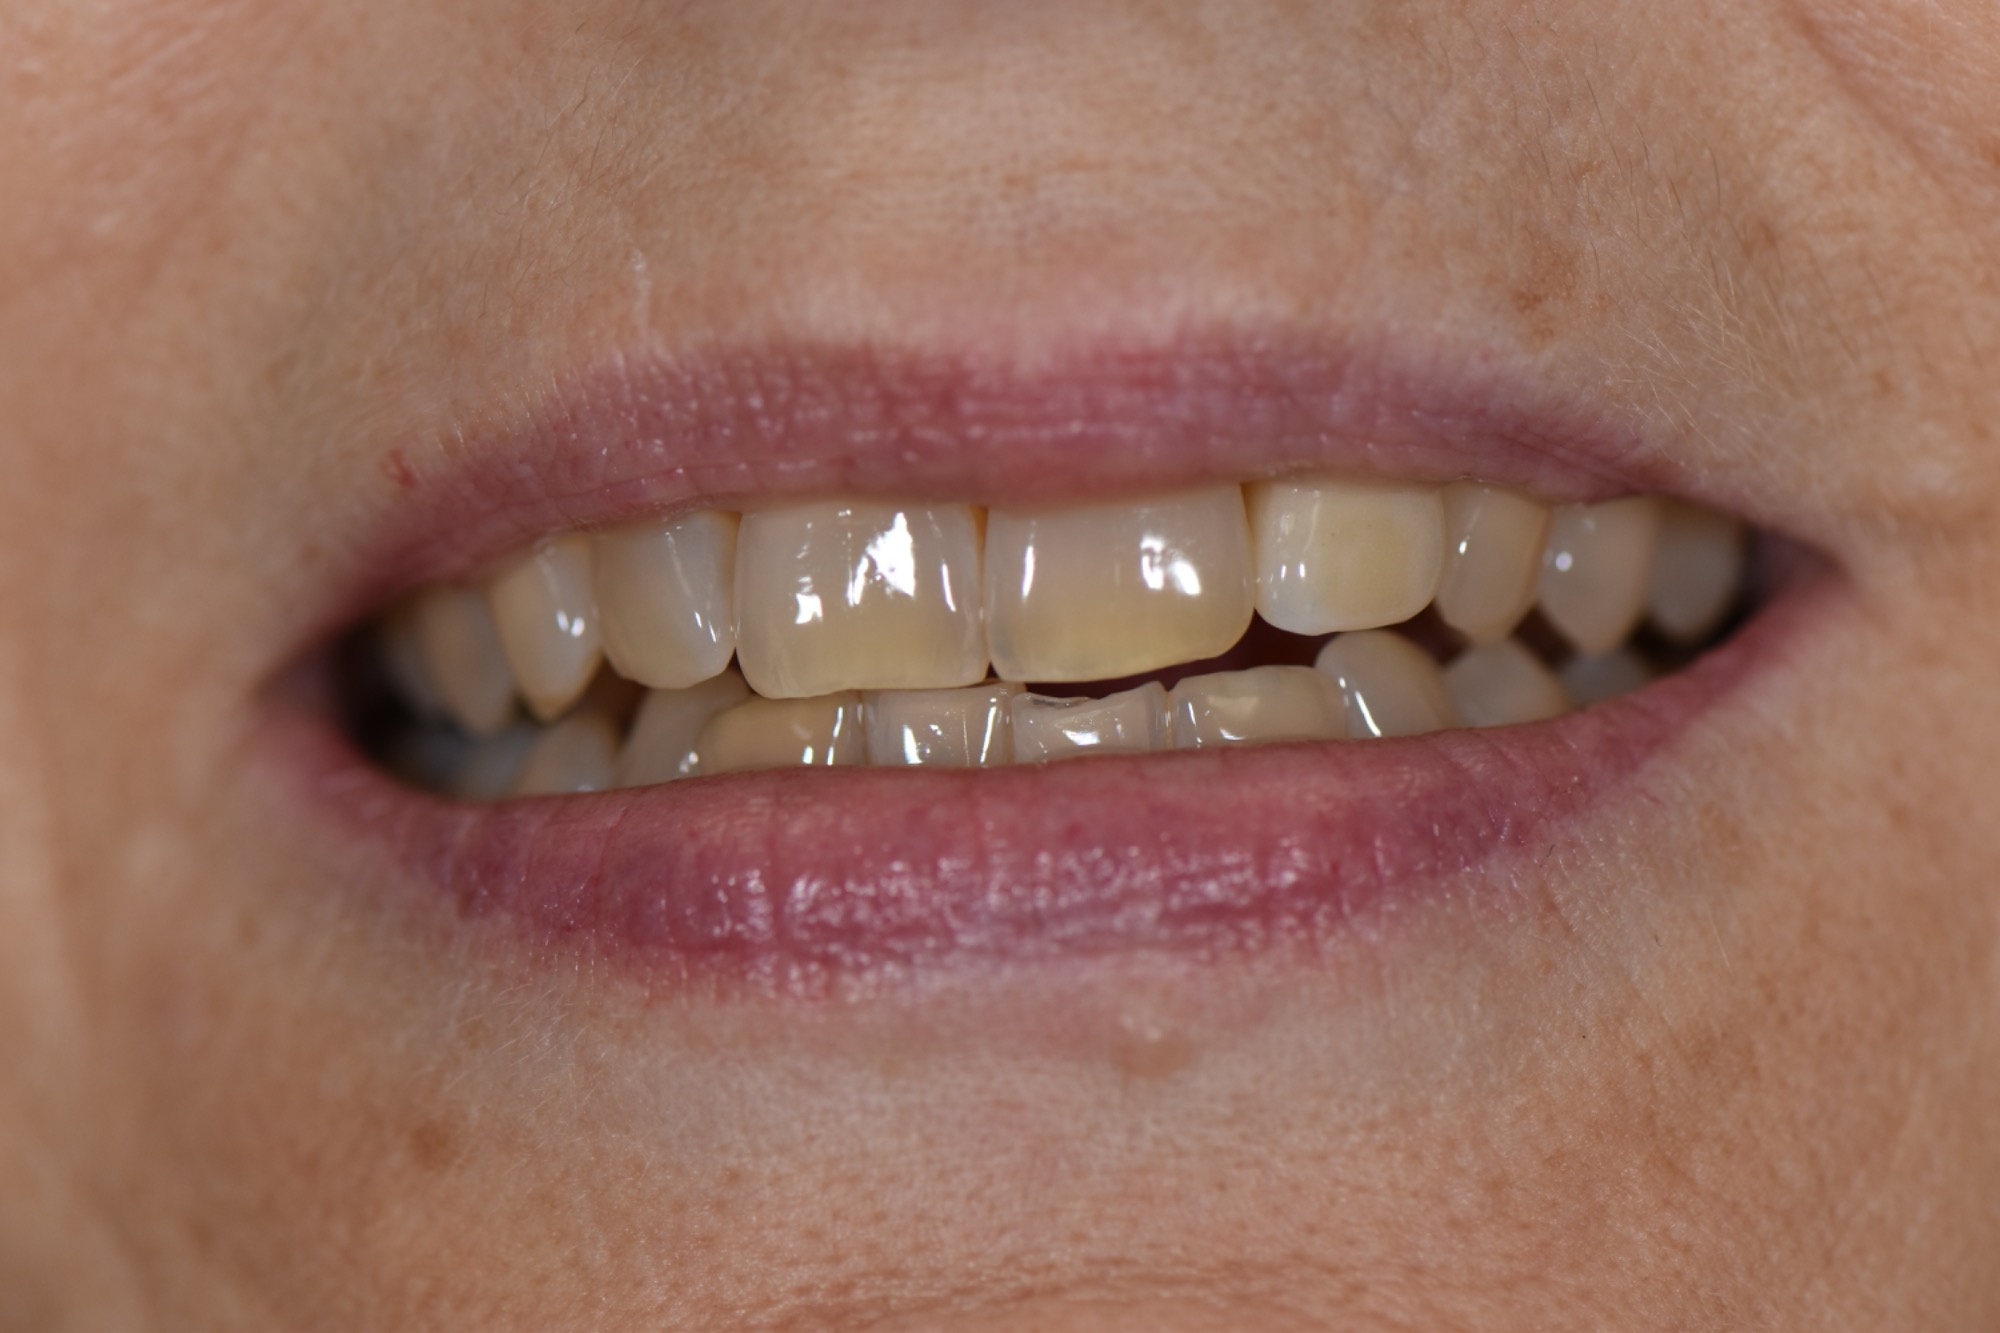

Frontzahnkronen Oberkiefer neu zur Verbesserung der Ästhetik.